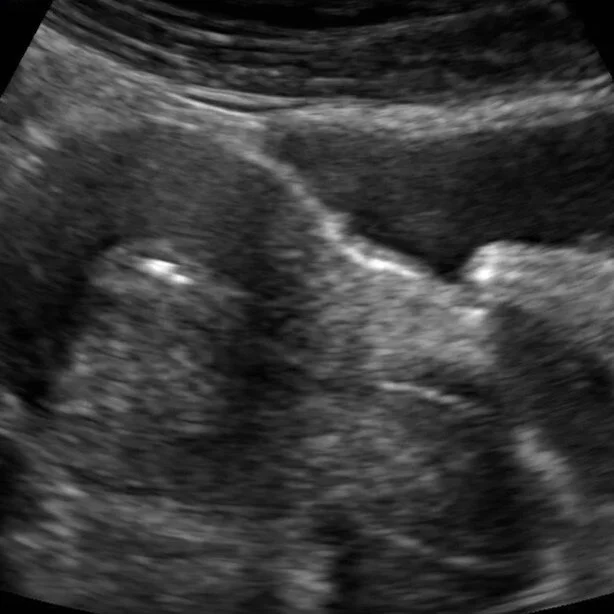

Transfer  Day

Emily Wittenauer 5/28/19 Emily Wittenauer 5/28/19